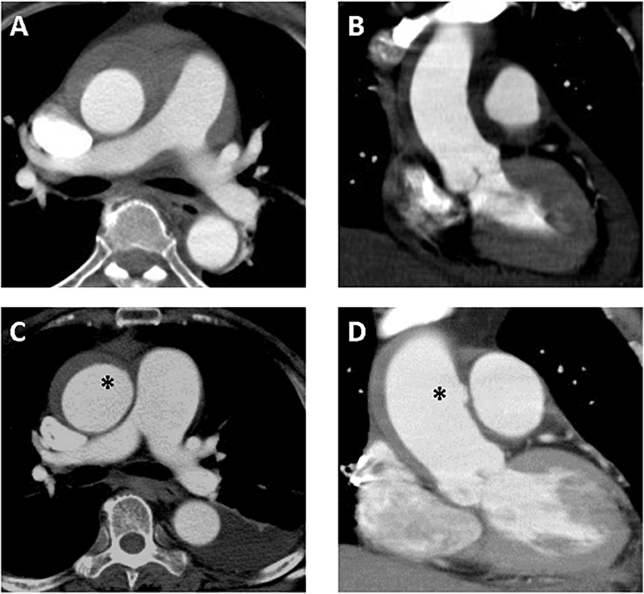

文献速递 | 急性a型主动脉壁内血肿的ct特征及临床意义

图片尺寸644x594